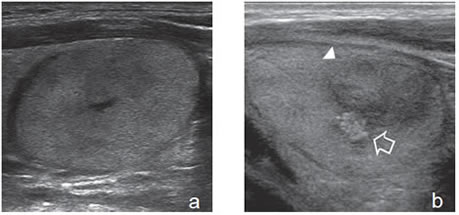

El parénquima tiroideo normal es de mayor ecogenicidad que los músculos pre-tiroideos. Los nódulos tiroideos pueden ser de menor ecogenicidad que el tejido glandular (hipoecogénicos), de ecogenicidad similar (isoecogénicos) o de mayor ecogenicidad (hiperecogénicos). La ecogenicidad de un nódulo se refiere al nivel de blanco, gris y negro que muestran en la imagen ecográfica (Figura 3a, b y c). La mayoría de los carcinomas papilares (75%-85%) son hipoecogénicos13. La hipoecogenicidad es un signo sensible pero inespecífico, ya que un 30% a 50% de los nódulos benignos14 también son hipoecogenicos (Figura 4). Sin embargo, si la hipoecogenicidad es acentuada (menor que la de los músculos pretiroideos), aumenta la sospecha de carcinoma (Figura 5). Los nódulos hiperecogénicos o isoecogenicos tienen mayor grado de asociación con lesiones hiperplásticas o foliculares benignas, y en mucho menor proporción con el cáncer papilar. Los nódulos puramente quísticos se definen como anecogénicos independiente de si muestran uno que otro fino septo aislado. Cuando el coloide se espesa, se forman microcristales que se ven como focos hiperecogénicos que contrastan con el fondo de coloide anecogénico, y generan un artefacto ultrasonográfico por reverberación, que produce una imagen posterior similar a la cola de un cometa (Figura 2a). La presencia de estos focos hiperecogénicos en un nódulo quístico indican la presencia de abundante coloide y se correlaciona con benignidad; prácticamente están ausentes en un nódulo maligno15.

Son tumores sólidos, únicos, iso o hiperecogénicos, muy homogéneos, encapsulados, de contornos lisos, de forma ovoidea, sin microcalcificaciones (Figura 3b). En el 80% de los casos se puede observar un halo hipoecogénico. Ocasionalmente pueden ser discretamente hipoecogénicos. La vascularización habitualmente esta aumentada en la periferia con vasos que se descuelgan hacia el centro de la lesión (Figura 12). A diferencia de los nódulos coloideos generalmente no se observan imágenes quísticas (Figura 32).